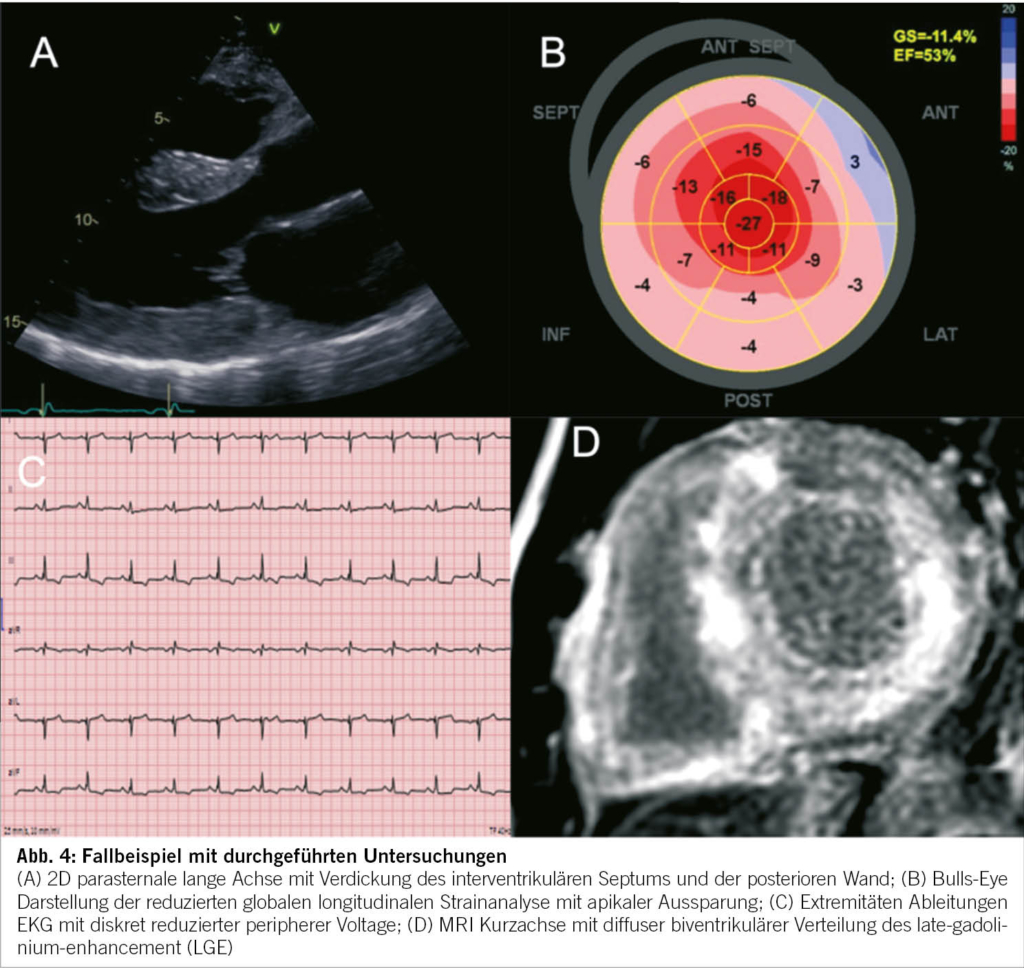

- Kardiomyopathien